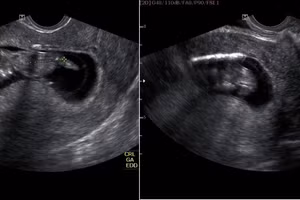

GD&TĐ - Bệnh nhân làm IVF đặt 1 phôi thai nhưng khi thăm khám phát hiện có thêm 1 khối thai khác nằm ngoài tử cung và may mắn được phẫu thuật kịp thời.